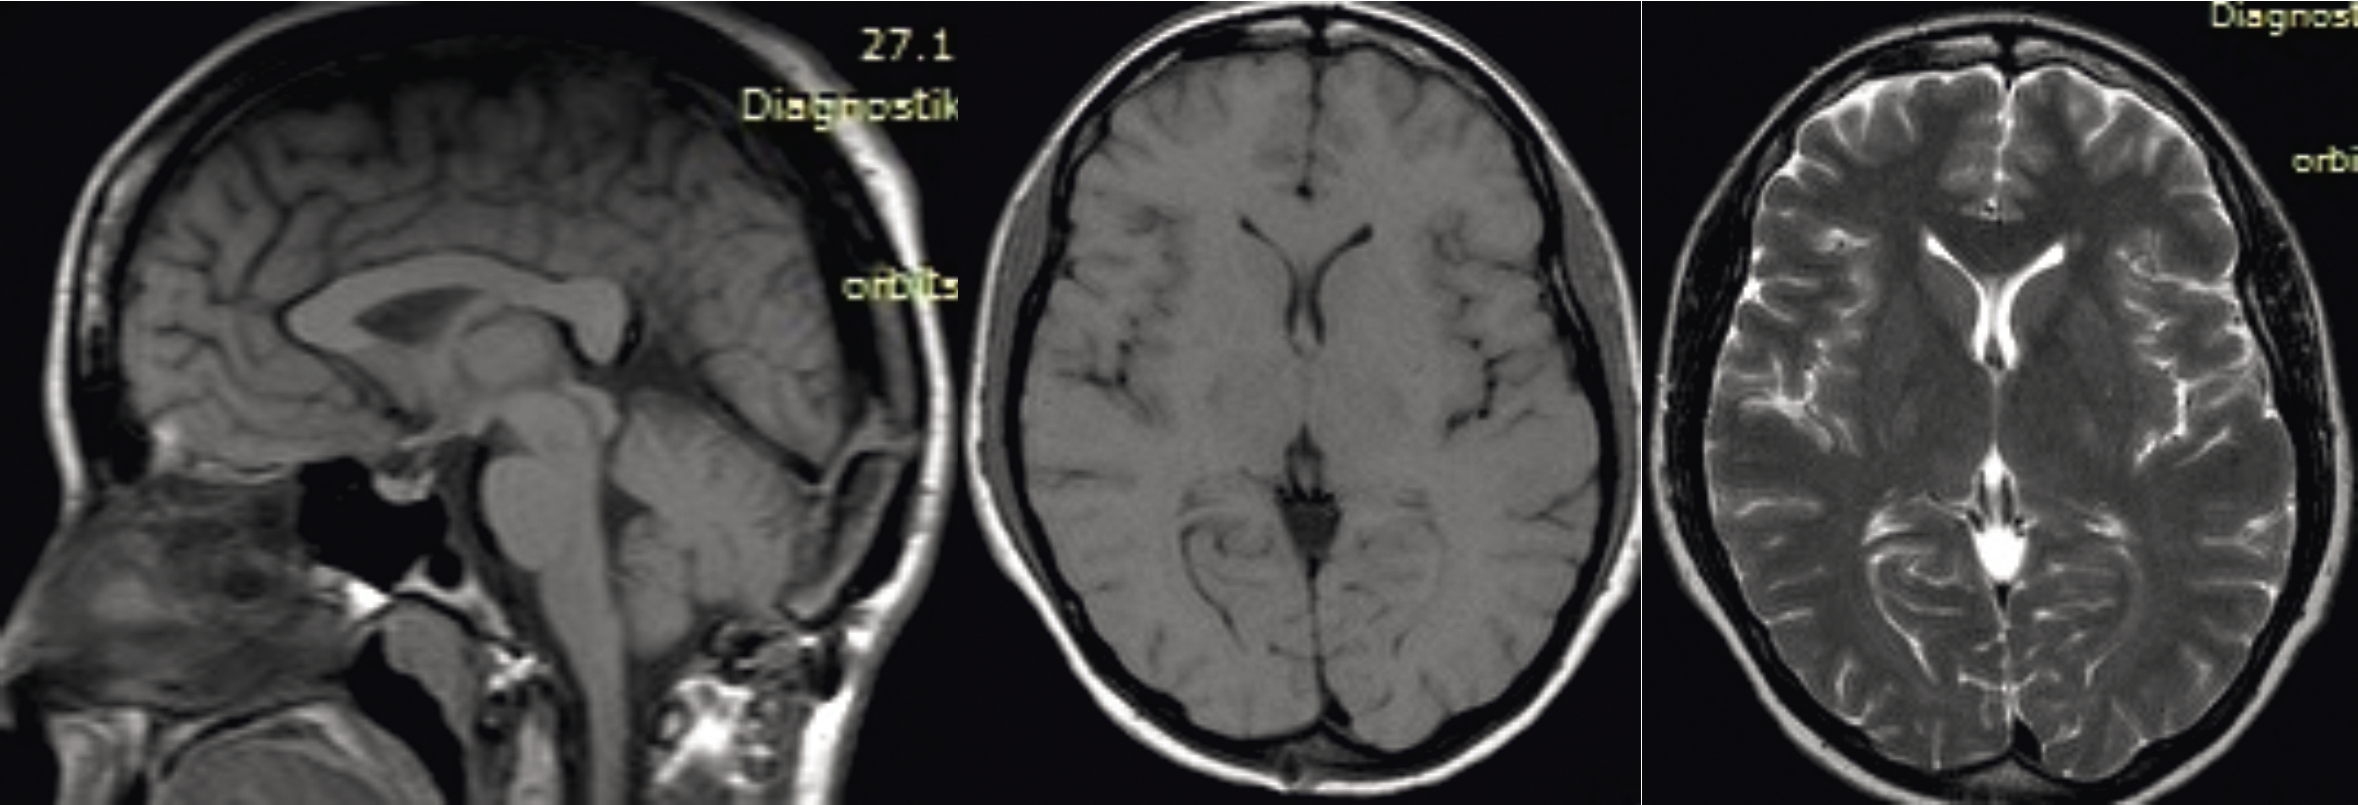

Приводим данные контрольного МРТ-исследования больной спустя 6 месяцев после операции и курса локальной лучевой терапии (нет признаков рецидива опухоли в зоне удаления, ликворопроводящие пути свободные) (рис. 4).

Рис. 4. МРТ головного мозга с внутривенным контрастированием после операции удаления опухоли эпифиза и курса лучевой терапии